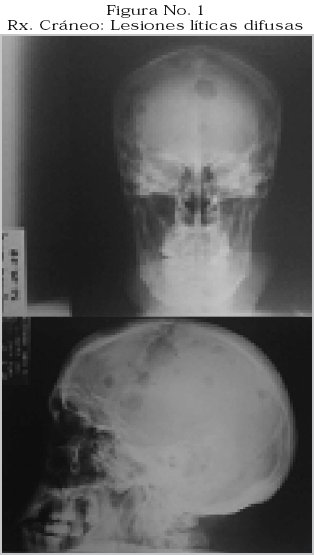

La radiografía de cráneo con imágenes osteolíticas redondeadas en "sacabocados" y múltiples, Figura No. 1.